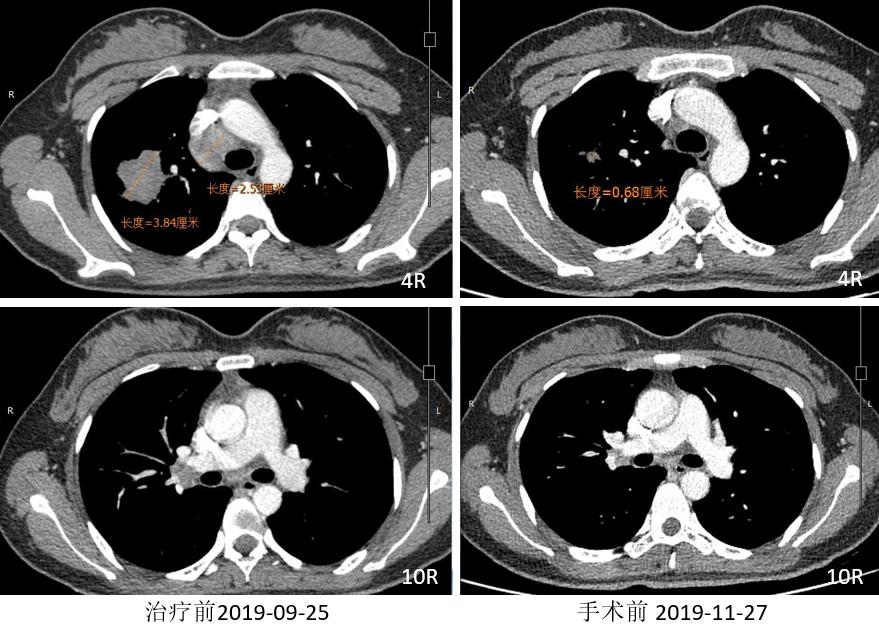

胸部CT

外周淋巴结CT

2019.12.10 行“右肺上叶切除术”。

术后病理:(右上叶)浸润性腺癌(腺管型95%,微乳头型5%),(纵隔4R组淋巴结)阴性。病灶内浸润性腺癌(约占20%),见较多区域纤维化伴组织细胞、淋巴细胞浸润,另见胆固醇结晶、多核巨细胞及肉芽肿反应,符合化疗后反应。